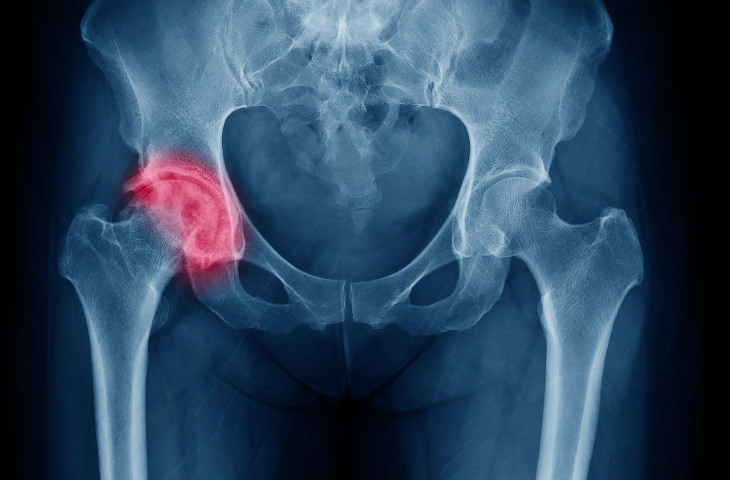

A labral tear is a tear in the soft tissue of a socket joint that normally supports and keeps in place the ball of the femur. Labral tears do not heal on their own and without surgery, movement can be limited and painful. If labral tears are not repaired or removed it can lead to early onset arthritis.

An arthroscopic procedure performed to remove torn labral tissue that is not amenable to repair. Two or three small incisions are made around the hip. An arthroscopic camera and instruments are introduced into the joint and used to identify the torn labrum. An arthroscopic shaver is then used to remove torn tissue leaving a smooth, uniform surface.